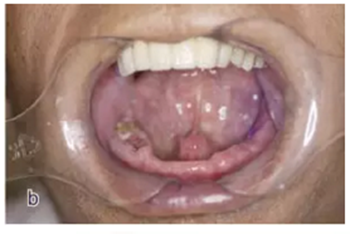

本案例為78歲男性患者,下頜義齒活動、固位差,口內(nèi)有殘根?;颊咭筮M(jìn)行種植義齒修復(fù)。

術(shù)前拍攝錐形束CT,進(jìn)行三維重建和種植方案規(guī)劃。從CT圖像中可以看出頜骨內(nèi)有骨島和殘根,為避免種植體植入骨島區(qū),考慮在兩側(cè)頦孔區(qū)種植4~5顆種植體,采用套筒冠進(jìn)行即刻修復(fù)。從重建的結(jié)果中可知前牙區(qū)牙槽嵴呈刀刃狀。種植方案為:對前牙區(qū)牙槽嵴進(jìn)行截骨修整,并在兩頦孔之間的區(qū)域內(nèi)植入5顆種植體。